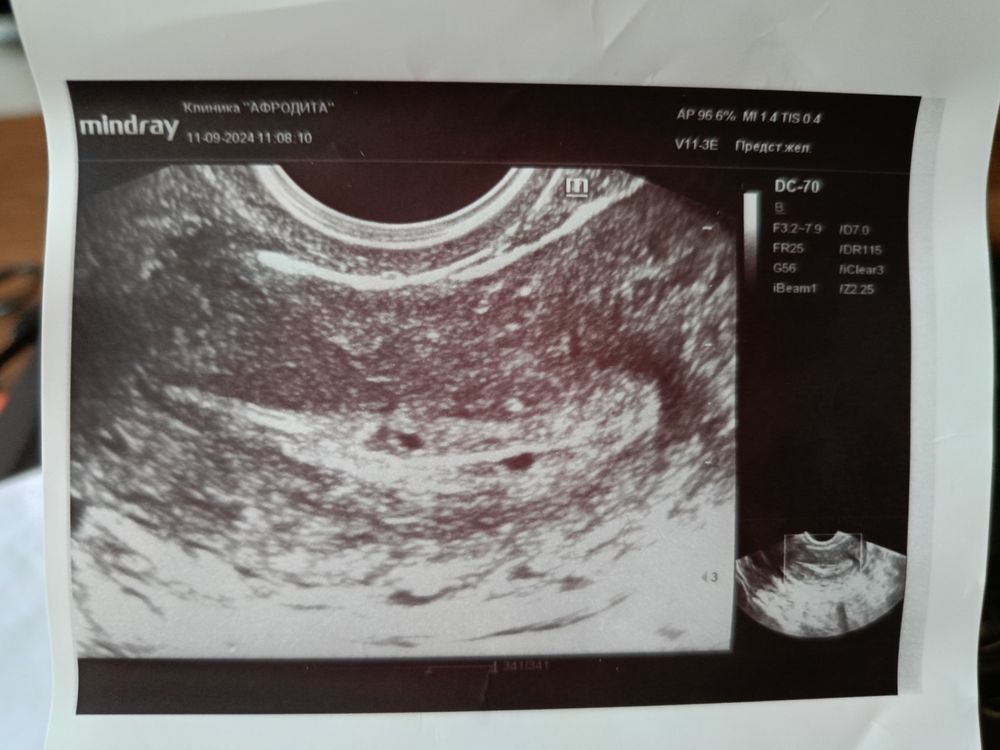

Многоплодная беременностьВсем привет! с 13.08 по 16.08 были месячные, 21.08 и 26.08 половые контакты. На второй день задержки 10.09 (месячные должны были начаться с 09.09) сделала тест и он показал две полоски, на следующий день сразу сходила на узи, там показало 2 округлых включения, хгч на тот день был 528.5, через 3 дня сдала еще один анализ он показал 1609. Девочки, это двойня? 🥺

Вот фото двойни на самом первом узи. На хгч не ориентируйтесь. Ваши похожи, но раз поставили под вопросом, значит нужно чуть подождать.

yamama, плюс 1.8 мм очень маленькие. У меня они были по 4,5 мм, но там и хгч был около 3х тыс